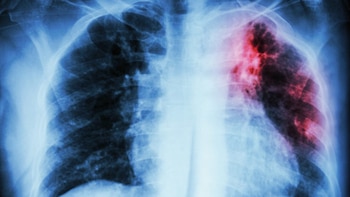

Comienza con dificultad para respirar y dolor en el pecho. Puede haber fiebre y tos con expectoración de sangre. Se trata de la Tuberculosis (TB), una enfermedad infectocontagiosa crónica producida por el bacilo de Koch, que se localiza generalmente en el pulmón, aunque puede afectar otros órganos.

Existen dos tipos de Tuberculosis: la pulmonar, que es la más frecuente y contagiosa, la cual representa alrededor del 80 al 85% del total de los casos; y la extrapulmonar, que afecta a otros órganos fuera del pulmón, como la pleura, ganglios, aparato genitourinario, columna, etc.

En el primer caso, la enfermedad se presenta con signos respiratorios como tos seca o productiva, expectoración con o sin hemoptisis, dolor torácico y síntomas generales como anorexia, astenia, adinamia, sudoración nocturna, pérdida de peso y a veces fiebre prolongada. En esta instancia, el paciente puede contagiar hasta tanto no haya iniciado un tratamiento, es por eso que toda persona que presente tos y catarro persistente por más de 15 días deberá ser estudiada para descartar la patología.

Según la experta, el diagnostico de la Tuberculosis se puede realizar a través de la bacteriología (baciloscopia), radiología, reacción de PPD (va a mostrar infección, aunque no enfermedad) y otras técnicas de laboratorio. Luego, la mayoría de los pacientes se cura en un periodo de seis meses o más de acuerdo a la categoría de la enfermedad si reciben tratamiento y lo cumplen de manera adecuada, preferentemente mediante esquemas de TAES (Tratamiento Estrictamente Supervisado) o TDO (Tratamiento Directamente Observado).